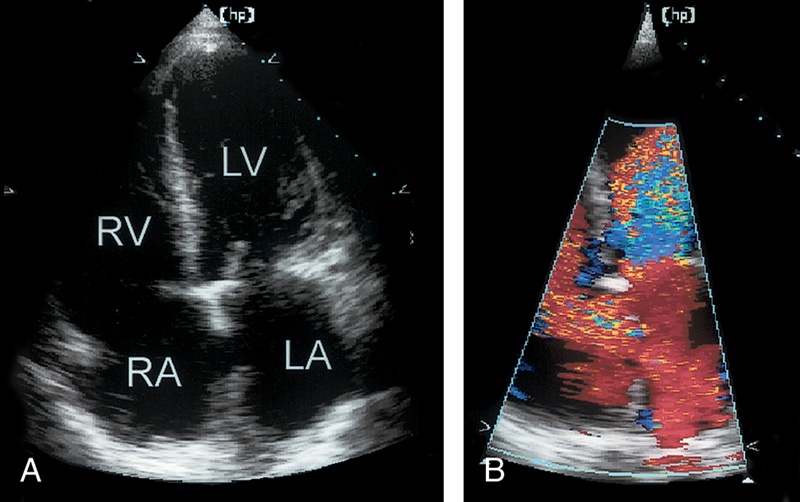

فحوصات تشخيصية لبعض امراض القلب والشرايين التاجية